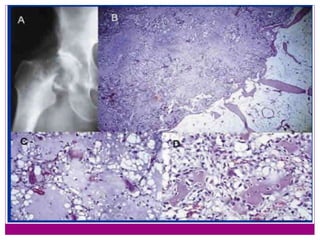

 A) Rx simple localizada del fémur: Se observa

fractura patológica sobre una lesión lítica

con permeación de la cortical y con

calcificaciones grumosas de tipo

condral.

 B) Pieza quirúrgica de condrosarcoma

desdiferenciado de costilla. Junto a áreas en

que el tumor presenta el característico

aspecto hialino, de un condrosarcoma

bien diferenciado, se observan zonas

de color pardo o amarillento

correspondientes a las áreas del componente

desdiferenciado.

 C) Visión microscópica panorámica que

muestra ambos componentes de

condrosarcoma: Bien diferenciado, en la

parte superior de la imagen, y del

componente desdiferenciado en la inferior.

Obsérvese la transición brusca entre ambos

componentes (x10, HE).

 D) Detalle del componente desdiferenciado

que presenta gran atipia celular y mitosis

atípicas (x100, HE).